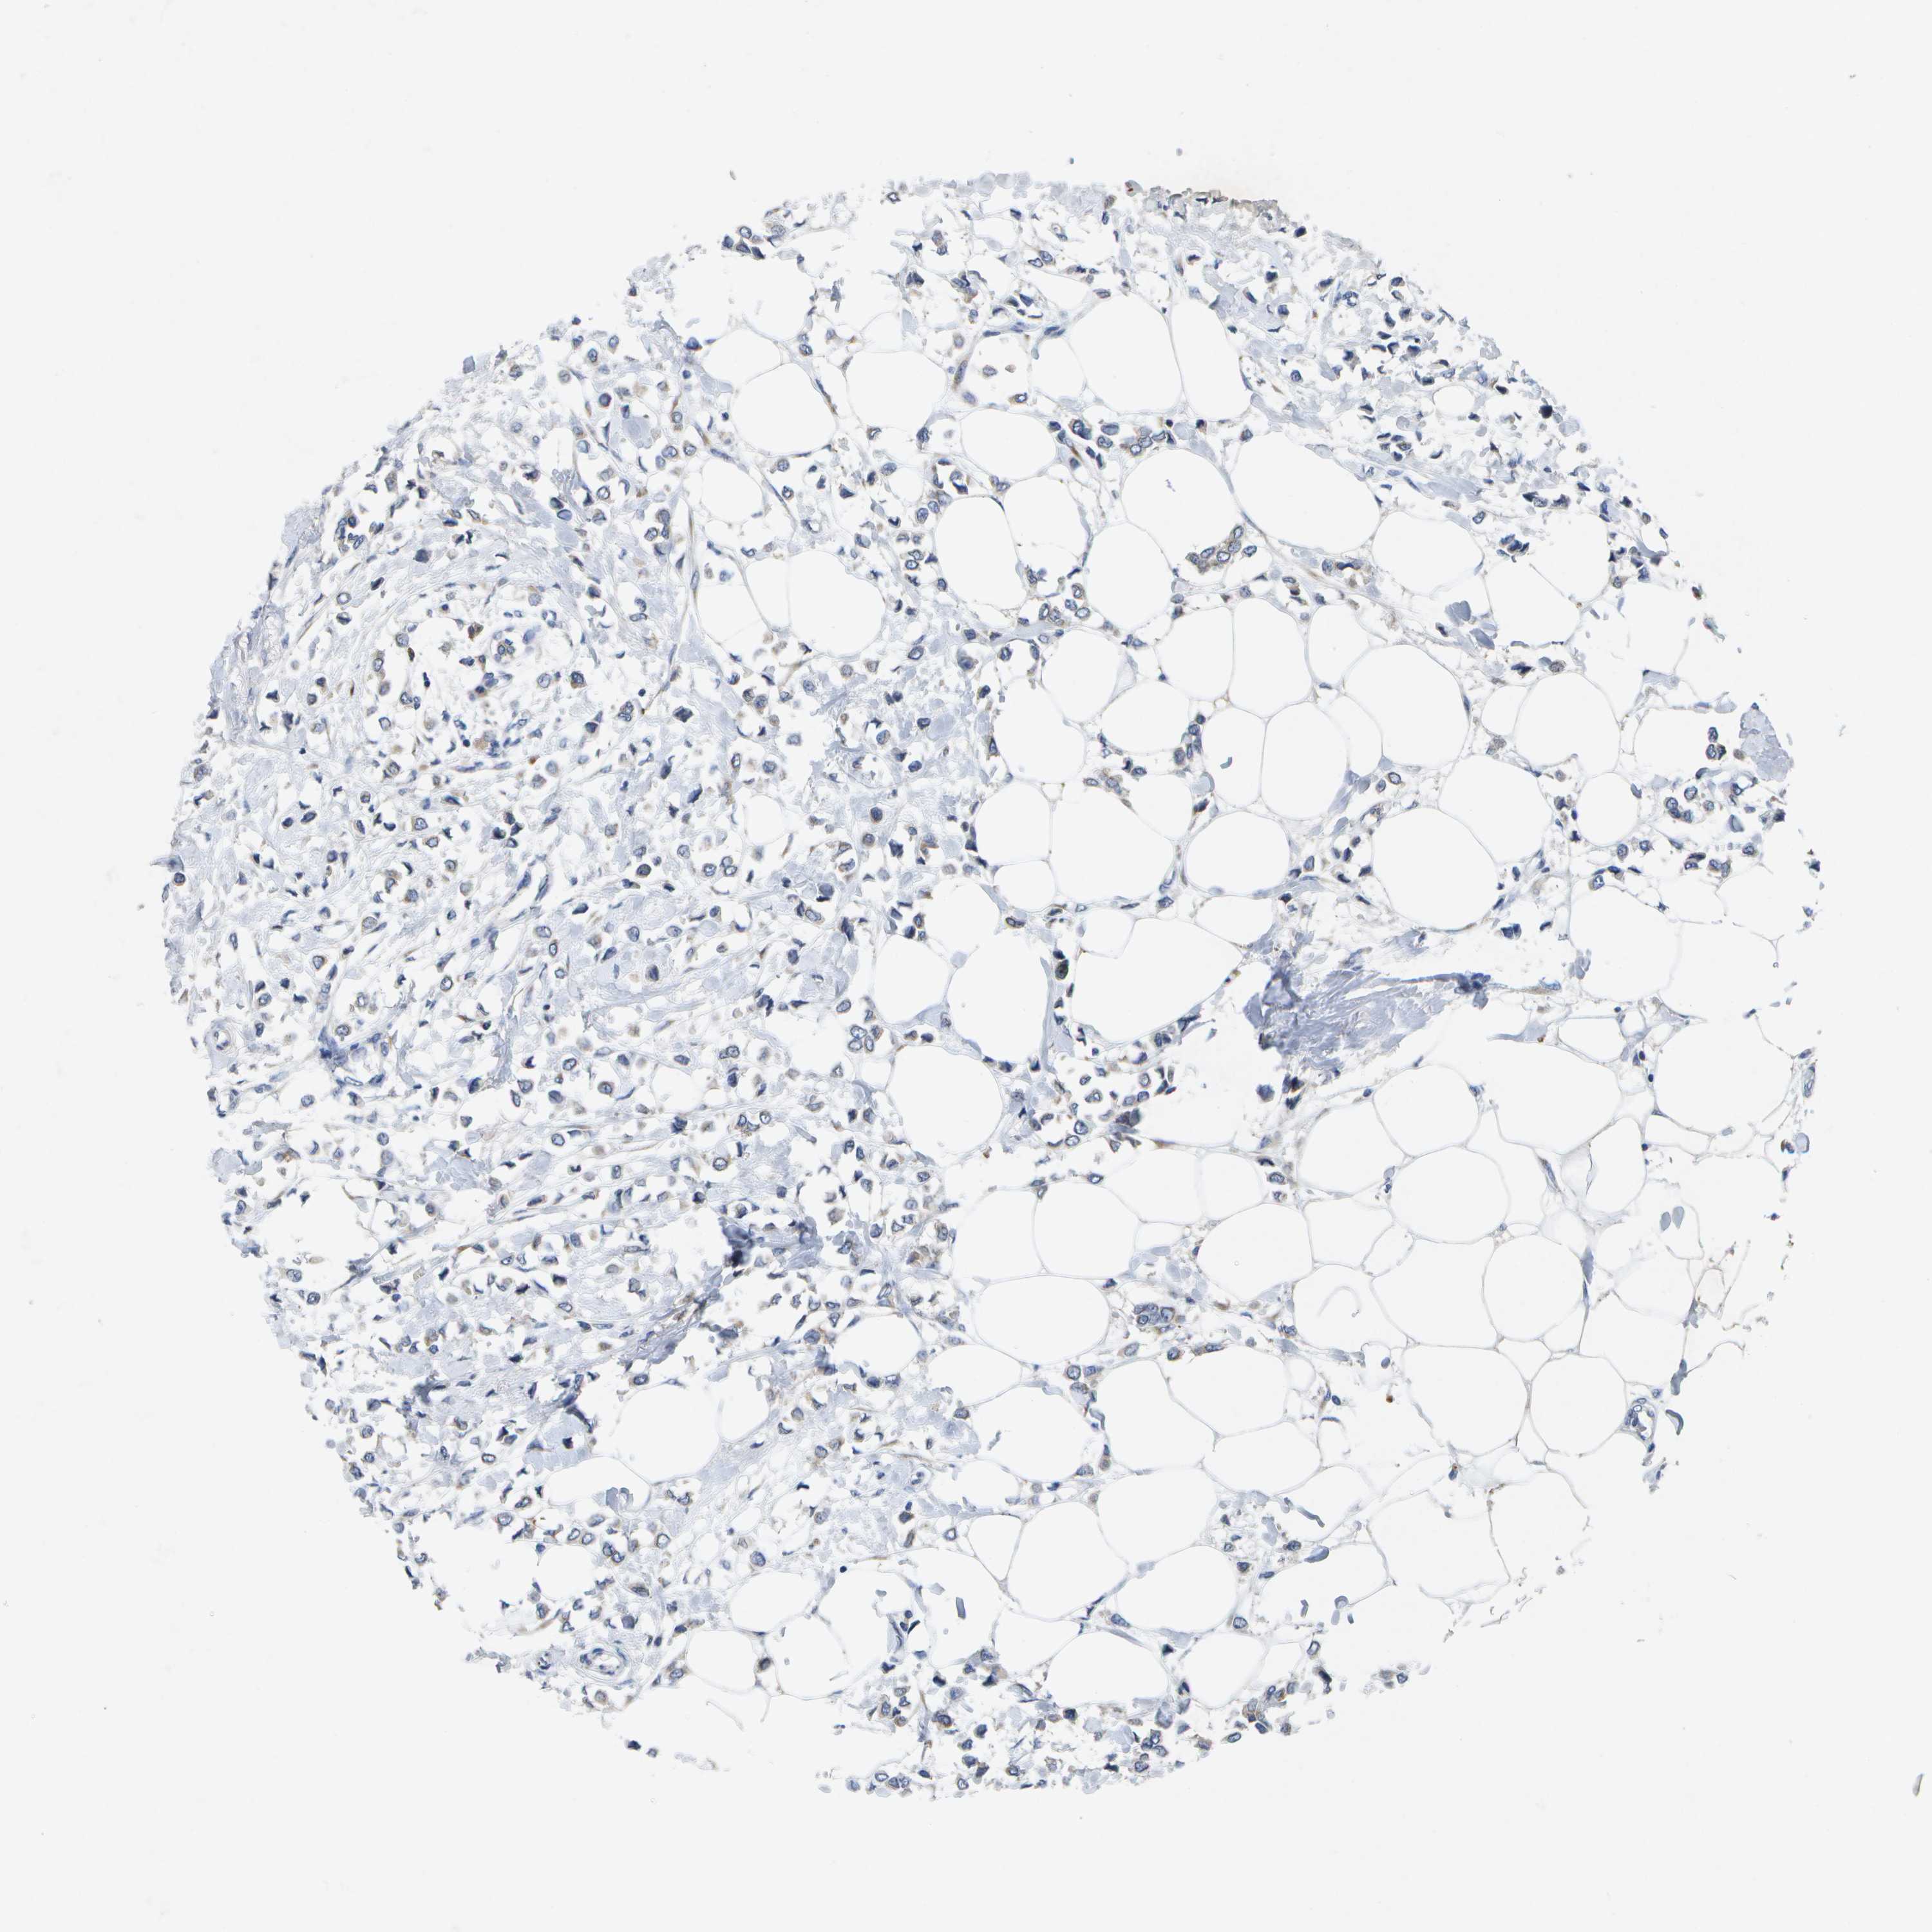

BRCA TCGA BRCA VALIDATION PROTEIN EXPRESSION